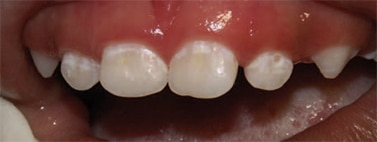

Severe ECC (S-ECC) is defined as any sign of smooth-surface caries in children younger than age 3. Additionally, in children ages 3 through 5, one or more dmf surfaces in primary maxillary anterior teeth, or a dmf score of ≥ 4 (age 3), ≥ 5 (age 4), or ≥ 6 (age 5) surfaces also constitutes S-ECC.3 The typical early sign of ECC is the crescent shaped white spot lesion at the gingival margin (Figure 1 to Figure 4).